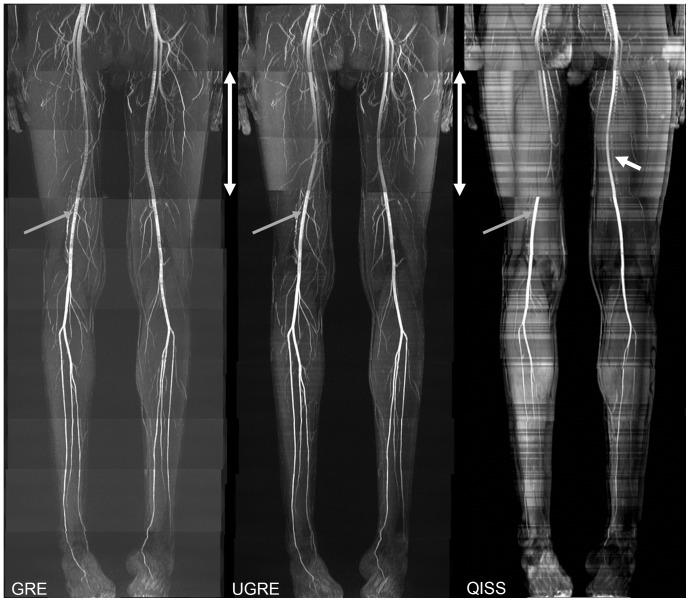

In this study three sequences for non-contrast-enhanced MRA of the lower extremity arteries at 7T were compared. Cardiac triggering was used with the aim to reduce signal variations in the arteries. Two fast single-shot 2D sequences, a modified Ultrafast Spoiled Gradient Echo (UGRE) sequence and a variant of the Quiescent-Interval Single-Shot (QISS) sequence were triggered via phonocardiogram and compared in volunteer examinations to a non-triggered 2D gradient echo (GRE) sequence. For image acquisition, a 16-channel transmit/receive coil and a manually positionable AngioSURF table were used. To tackle B1 inhomogeneities at 7T, Time-Interleaved Acquisition of Modes (TIAMO) was integrated in GRE and UGRE. To compare the three sequences quantitatively, a vessel-to-background ratio (VBR) was measured in all volunteers and stations. In conclusion, cardiac triggering was able to suppress flow artifacts satisfactorily. The modified UGRE showed only moderate image artifacts. Averaged over all volunteers and stations, GRE reached a VBR of 4.18±0.05, UGRE 5.20±0.06, and QISS 2.72±0.03. Using cardiac triggering and TIAMO imaging technique was essential to perform non-enhanced MRA of the lower extremities vessels at 7T. The modified UGRE performed best, as observed artifacts were only moderate and the highest average VBR was reached.

本研究比较了 7T 下肢动脉非对比增强 MRA 的三种序列。采用心电触发以减少动脉信号变化。两种快速单次 2D 序列,一种改良的超快扰相梯度回波(UGRE)序列和一种 Quiet-Interval Single-Shot(QISS)序列通过心音触发,并在志愿者检查中与非触发的 2D 梯度回波(GRE)序列进行比较。图像采集使用 16 通道发射/接收线圈和手动定位的 AngioSURF 表。为了解决 7T 下的 B1 不均匀性,在 GRE 和 UGRE 中集成了 Time-Interleaved Acquisition of Modes(TIAMO)。为了定量比较三种序列,在所有志愿者和站位测量血管与背景比(VBR)。总之,心电触发能够很好地抑制流动伪影。改良的 UGRE 仅显示中度图像伪影。在所有志愿者和站位的平均值中,GRE 达到 4.18±0.05,UGRE 为 5.20±0.06,QISS 为 2.72±0.03。使用心电触发和 TIAMO 成像技术对于在 7T 下进行下肢血管非增强 MRA 至关重要。改良的 UGRE 表现最佳,因为观察到的伪影仅为中度,并且达到了最高的平均 VBR。